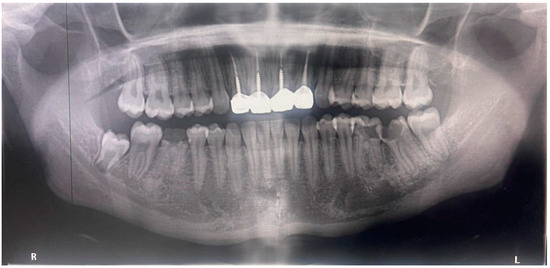

2.5. Results